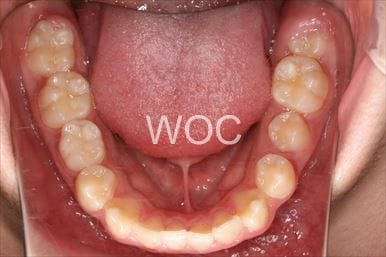

治療後1

治療後2

治療後3

治療後4

治療後5

- 年齢:23歳女性

- 主訴:出っ歯、口が閉じにくい

- 基本矯正料金:895,000円

- 治療期間:1年10ヶ月

- 非抜歯